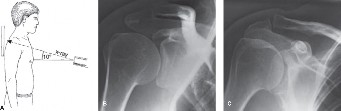

Crack the Case: Bony Bankart Hillsachs Shoulder Injuries

A 33-year-old male presents to the ED after a fall during a soccer game. He reports significant right shoulde…